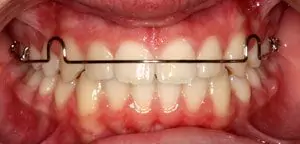

Orthodontic Case – II

(Case Done by Dr. Sonali Deshmukh M.D.S. / Orthodontist )

Correction Of Protruded

Small Lower Jaw

A child with protruded teeth and a small lower jaw at a young age can be treated by Myofunctional appliances which help in the growth of the jaw.

Pre Treatment

After Myofunctional appliances therapy for jaw growth accompanied by braces treatment for correction of protruded teeth.